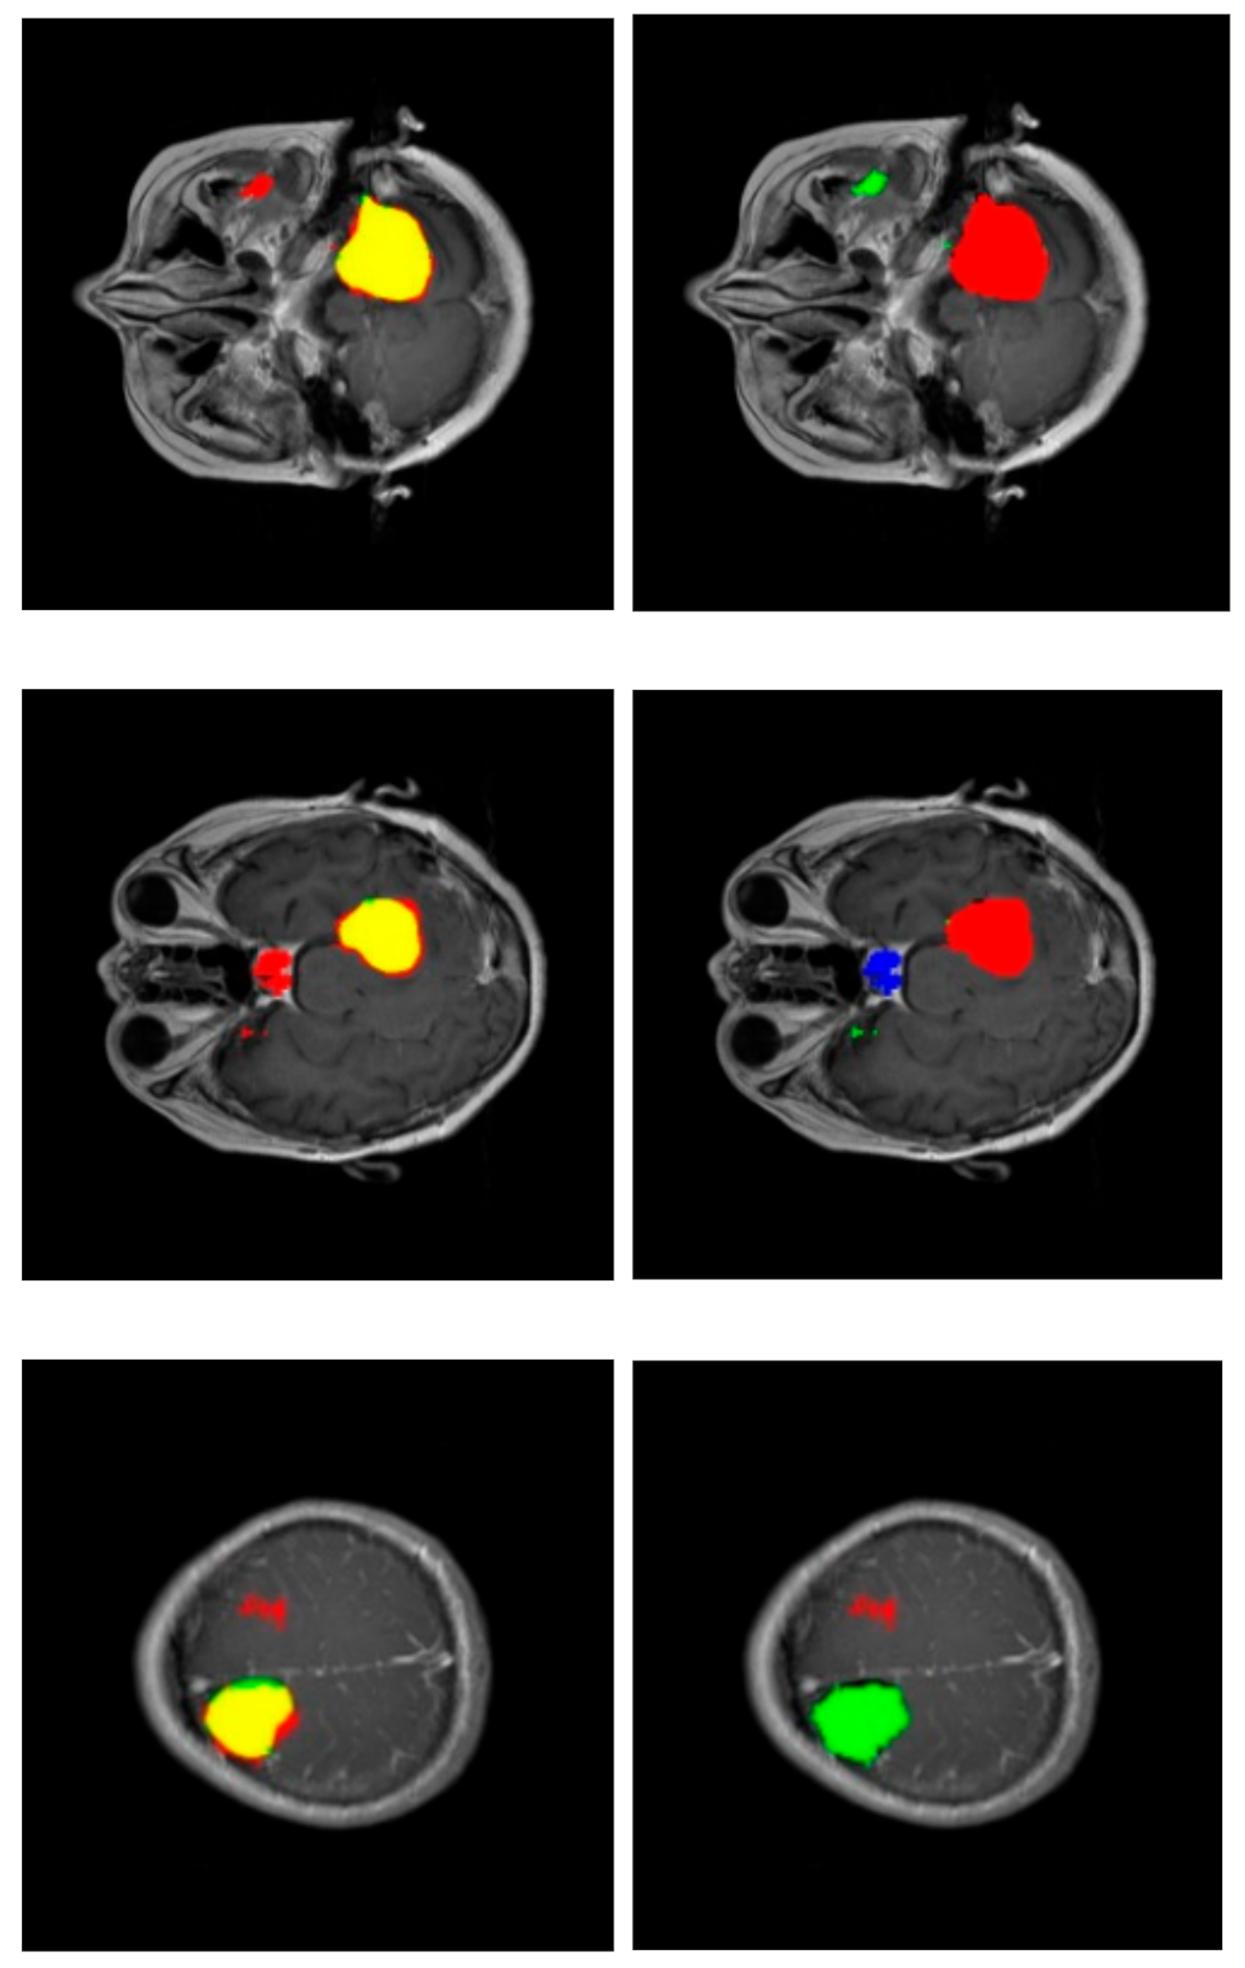

Figure 6 shows some segmentations with misclassified areas; in the example of the upper row, the greater part of the detected tumor is correctly labeled (red area in the right column), resulting in a very correct segmentation (yellow area in the left column). However, there is a region detected in the non-cerebral area wrongly labeled as glioma tumor (green area in the right column). This example shows the added complexity inherent to this dataset due to the fact that it includes non-cerebral areas that can generate false positives. This complexity also manifests itself in the example of the middle row. Similarly, the segmentation is relatively correct (yellow region in the left column), but there is a misclassified area labeled as a pituitary tumor (blue region in the right column) located in the sphenoidal sinuses area, which is where pituitary tumors appear. The physical structure of the sphenoidal sinuses led to confusion to our model. The third example (lower row) shows a confusion between a real glioma (green region in the right column) and a wrongly predicted meningioma region (red area in the left column).

Figure 6.

Confusion in segmentation. Color-generated images for proper visualization of regions. Upper row corresponds to a meningioma tumor, middle row to a meningioma tumor, and lower row to a glioma tumor. Right column shows the predicted tumor tags (red: meningioma, green: glioma, blue: pituitary tumor). Left column shows segmentations (red: predicted, green: ground truth and, as a result, the intersection is shown in yellow).